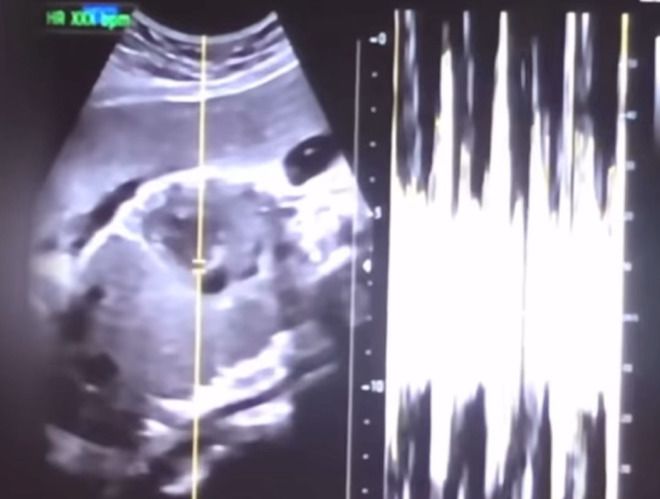

낙태한 산모의 유튜브 동영상에서 캡쳐한 초음파 사진과 심박 그래프. [사진=서울중앙지검]